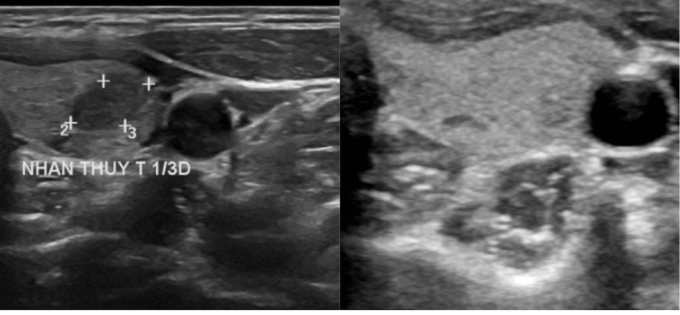

Khối u của chị Kiều trước điều trị (bên trái) và sau 12 tháng đốt sóng cao tần (bên phải) biến mất hoàn toàn. Ảnh: Bệnh viện Đa khoa Tâm Anh

12 tháng sau chị Kiều tái khám,siêu âm cho thấy khối u biến mất,không tái phát,không di căn hạch,tuyến giáp được bảo tồn nguyên vẹn.

Ngày 29/10,bác sĩ Khánh cho hay thông thường phương pháp điều trị ung thư tuyến giáp phổ biến là phẫu thuật cắt bán phần hoặc toàn bộ tuyến giáp. Sau đó người bệnh uống thuốc iốt để tránh ung thư tái phát và uống hormone tuyến giáp suốt đời. Trường hợp chị Kiều,khối u kích thước dưới 1 cm,cách xa vỏ bao tuyến giáp hơn 5 mm và siêu âm chưa thấy hạch di căn. Do đó,bác sĩ lựa chọn phương pháp đốt sóng cao tần (RFA) để bảo tồn tối đa tuyến giáp bệnh nhân.

Để điều trị cho chị Kiều,dưới hướng dẫn siêu âm bác sĩ đưa kim đốt xuyên qua da,tiếp cận khối u. Nhiệt từ dòng điện xoay chiều ở đầu kim đốt cháy các mô xung quanh gây hoại tử,theo thời gian u teo nhỏ dần.

Sau 20 phút đốt điện,khối u mất hoàn toàn,người bệnh xuất viện ngay trong ngày. Đến nay,sau một năm,u không tái phát,bác sĩ Khánh cho rằng kết quả này tương đồng với nhiều nghiên cứu trên thế giới. Ví dụ,nghiên cứu của Hội tuyến giáp Mỹ công bố năm 2022,tổng hợp các báo cáo về điều trị ung thư tuyến giáp bằng sóng cao tần RFA trên 1.770 bệnh nhân,cho thấy 79% trường hợp ung thư biến mất hoàn toàn,khoảng 0,4% nhân vẫn tiến triển sau đốt. Kết quả này được đưa ra sau thời gian trung bình 33 tháng theo dõi bệnh nhân đốt RFA.